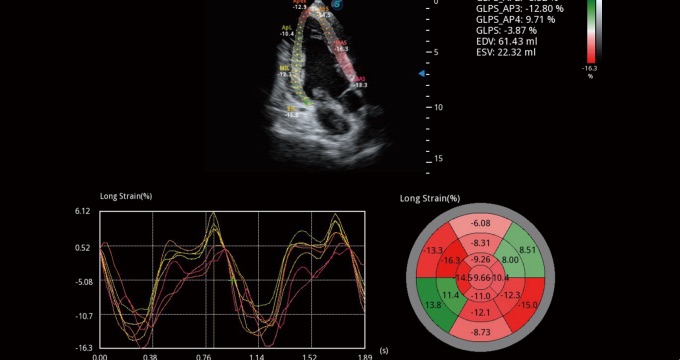

通过心肌识别技术和二维斑点追踪技术相结合,计算心肌各节段的应变应变率、速度、位移并以曲线图显示,实现整体或者局部心肌定量分析。同时可呈现牛眼图直观和准确诊断心肌的运动情况。